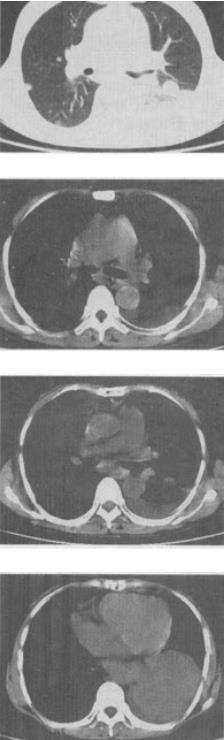

- 单项选择题 女,55岁,胸痛伴咯血丝痰1周,胸部CT如图,最可能的诊断为()。

B、左侧周围型肺癌并肺内转移

- B